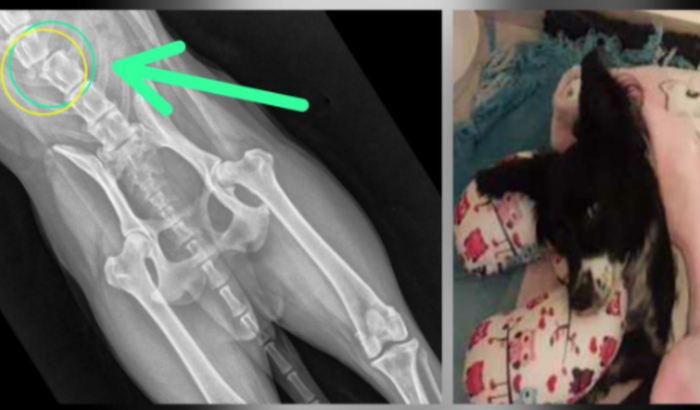

Olá! Eu Sou a Annabbel,  sofri um grave acidente e tive uma lesão na coluna.  Estou fazendo um tratamento com medicações caras e preciso de fisioterapia, além  de um carrinho para voltar a me movimentar, e talvez de uma provável cirurgia a ver tudo

• Olá! Eu Sou a Annabbel,  sofri um grave acidente e tive uma lesão na coluna.

• Estou fazendo um tratamento com medicações caras e preciso de fisioterapia, além  de um carrinho para voltar a me movimentar, e talvez de uma provável cirurgia a depender da resposta das medicações.

• O tratamento será longo, mas vai dar certo ! 💚